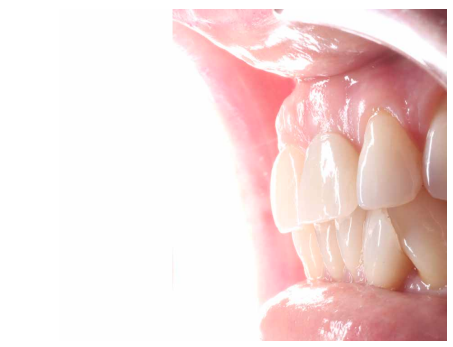

Conclusiones: La rehabilitación sobre implantes en situaciones de pérdida dental en el sector anterior estético y en especial, en pacientes jóvenes, requiere un plan de tratamiento multidisciplinar en cuanto a la extracción del diente y colocación del IOI en la posición tridimensional correcta, existiendo diferentes aspectos a tener en cuenta para ello, especialmente el remanente óseo residual, la posición del margen gingival, así como la preservación y acondicionamiento de los tejidos duros y blandos periimplantarios mediante injertos y un manejo correcto de una prótesis provisional hasta conseguir un perfil de emergencia y contorno gingival ideal antes de la corona definitiva

Conclusions: Rehabilitation on implants in situations of tooth loss in the aesthetic anterior sector, especially in young patients, requires a multidisciplinary treatment plan in relation to tooth extraction and placement of the OII in the correct three-dimensional position. There are various aspects to be taken into account, particularly the residual remaining bone, the position of the gingival margin, as well as the preservation and conditioning of the peri-implant hard and soft tissues by means of grafts and proper handling of a provisional prosthesis until an ideal emergence profile and gingival contour is achieved before the final crown.